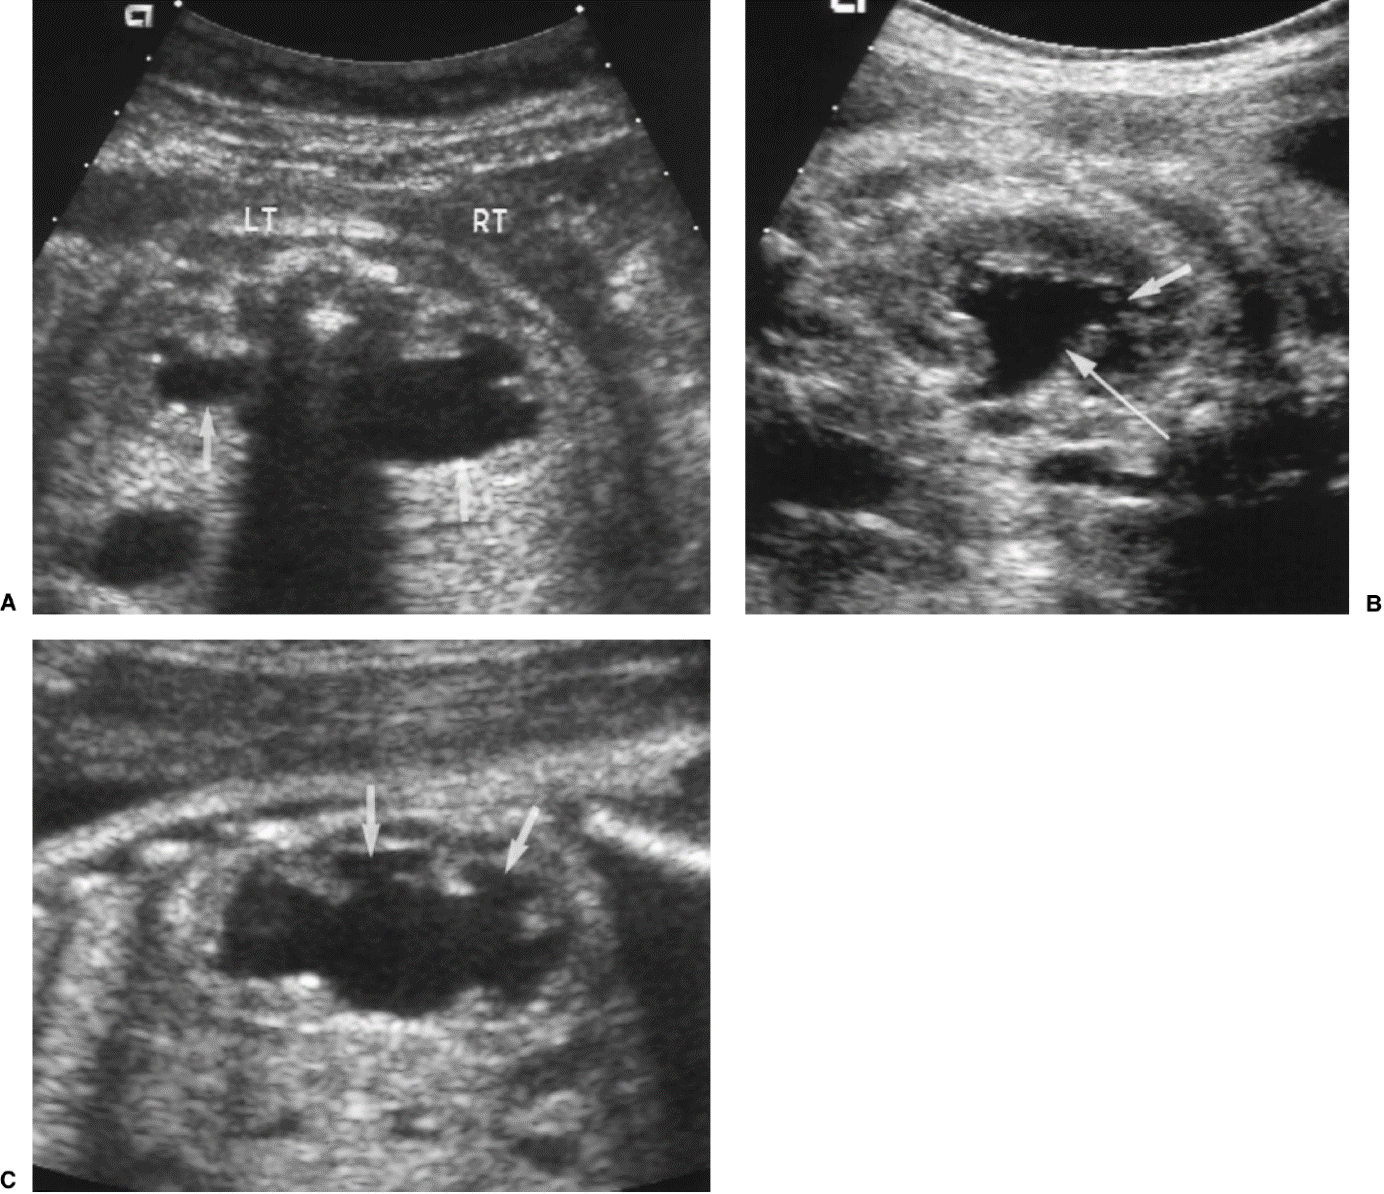

Veel ernstige vormen van urethrakleppen worden al gezien bij echografisch onderzoek vóór de geboorte. Bij de 20 weken echo (of misschien in de toekomst bij een 13 weken echo) worden verwijde nierbekkens en urineleiders gezien. De blaas kan dikwandig zijn, maar ook zeer groot en uitgerekt. Vaak kan het verwijde deel van de plasbuis ónder de blaas worden gezien. Dat noemen we het “sleutelgat teken” omdat de blaas in lengtedoorsnede op de echo er dan uitziet als een sleutelgat. De hoeveelheid vruchtwater kan normaal of verminderd zijn. Als er een verdenking is op urethrakleppen wordt de bevalling gedaan in een centrum waar direct optimale zorg kan worden geleverd aan de pasgeborene.

20 weken echografie: links: dikwandige blaas met verwijding van de plasbuis tot aan de kleppen (pijl): het “sleutelgat teken”. Onder: verwijde urineleiders. Bij kinderen gaan de urineleiders bij verwijding ook erg gekronkeld verlopen.

Verwijde nierbekkens (lange pijl) en nierkelkjes (korte pijl). Smalle nierschors.